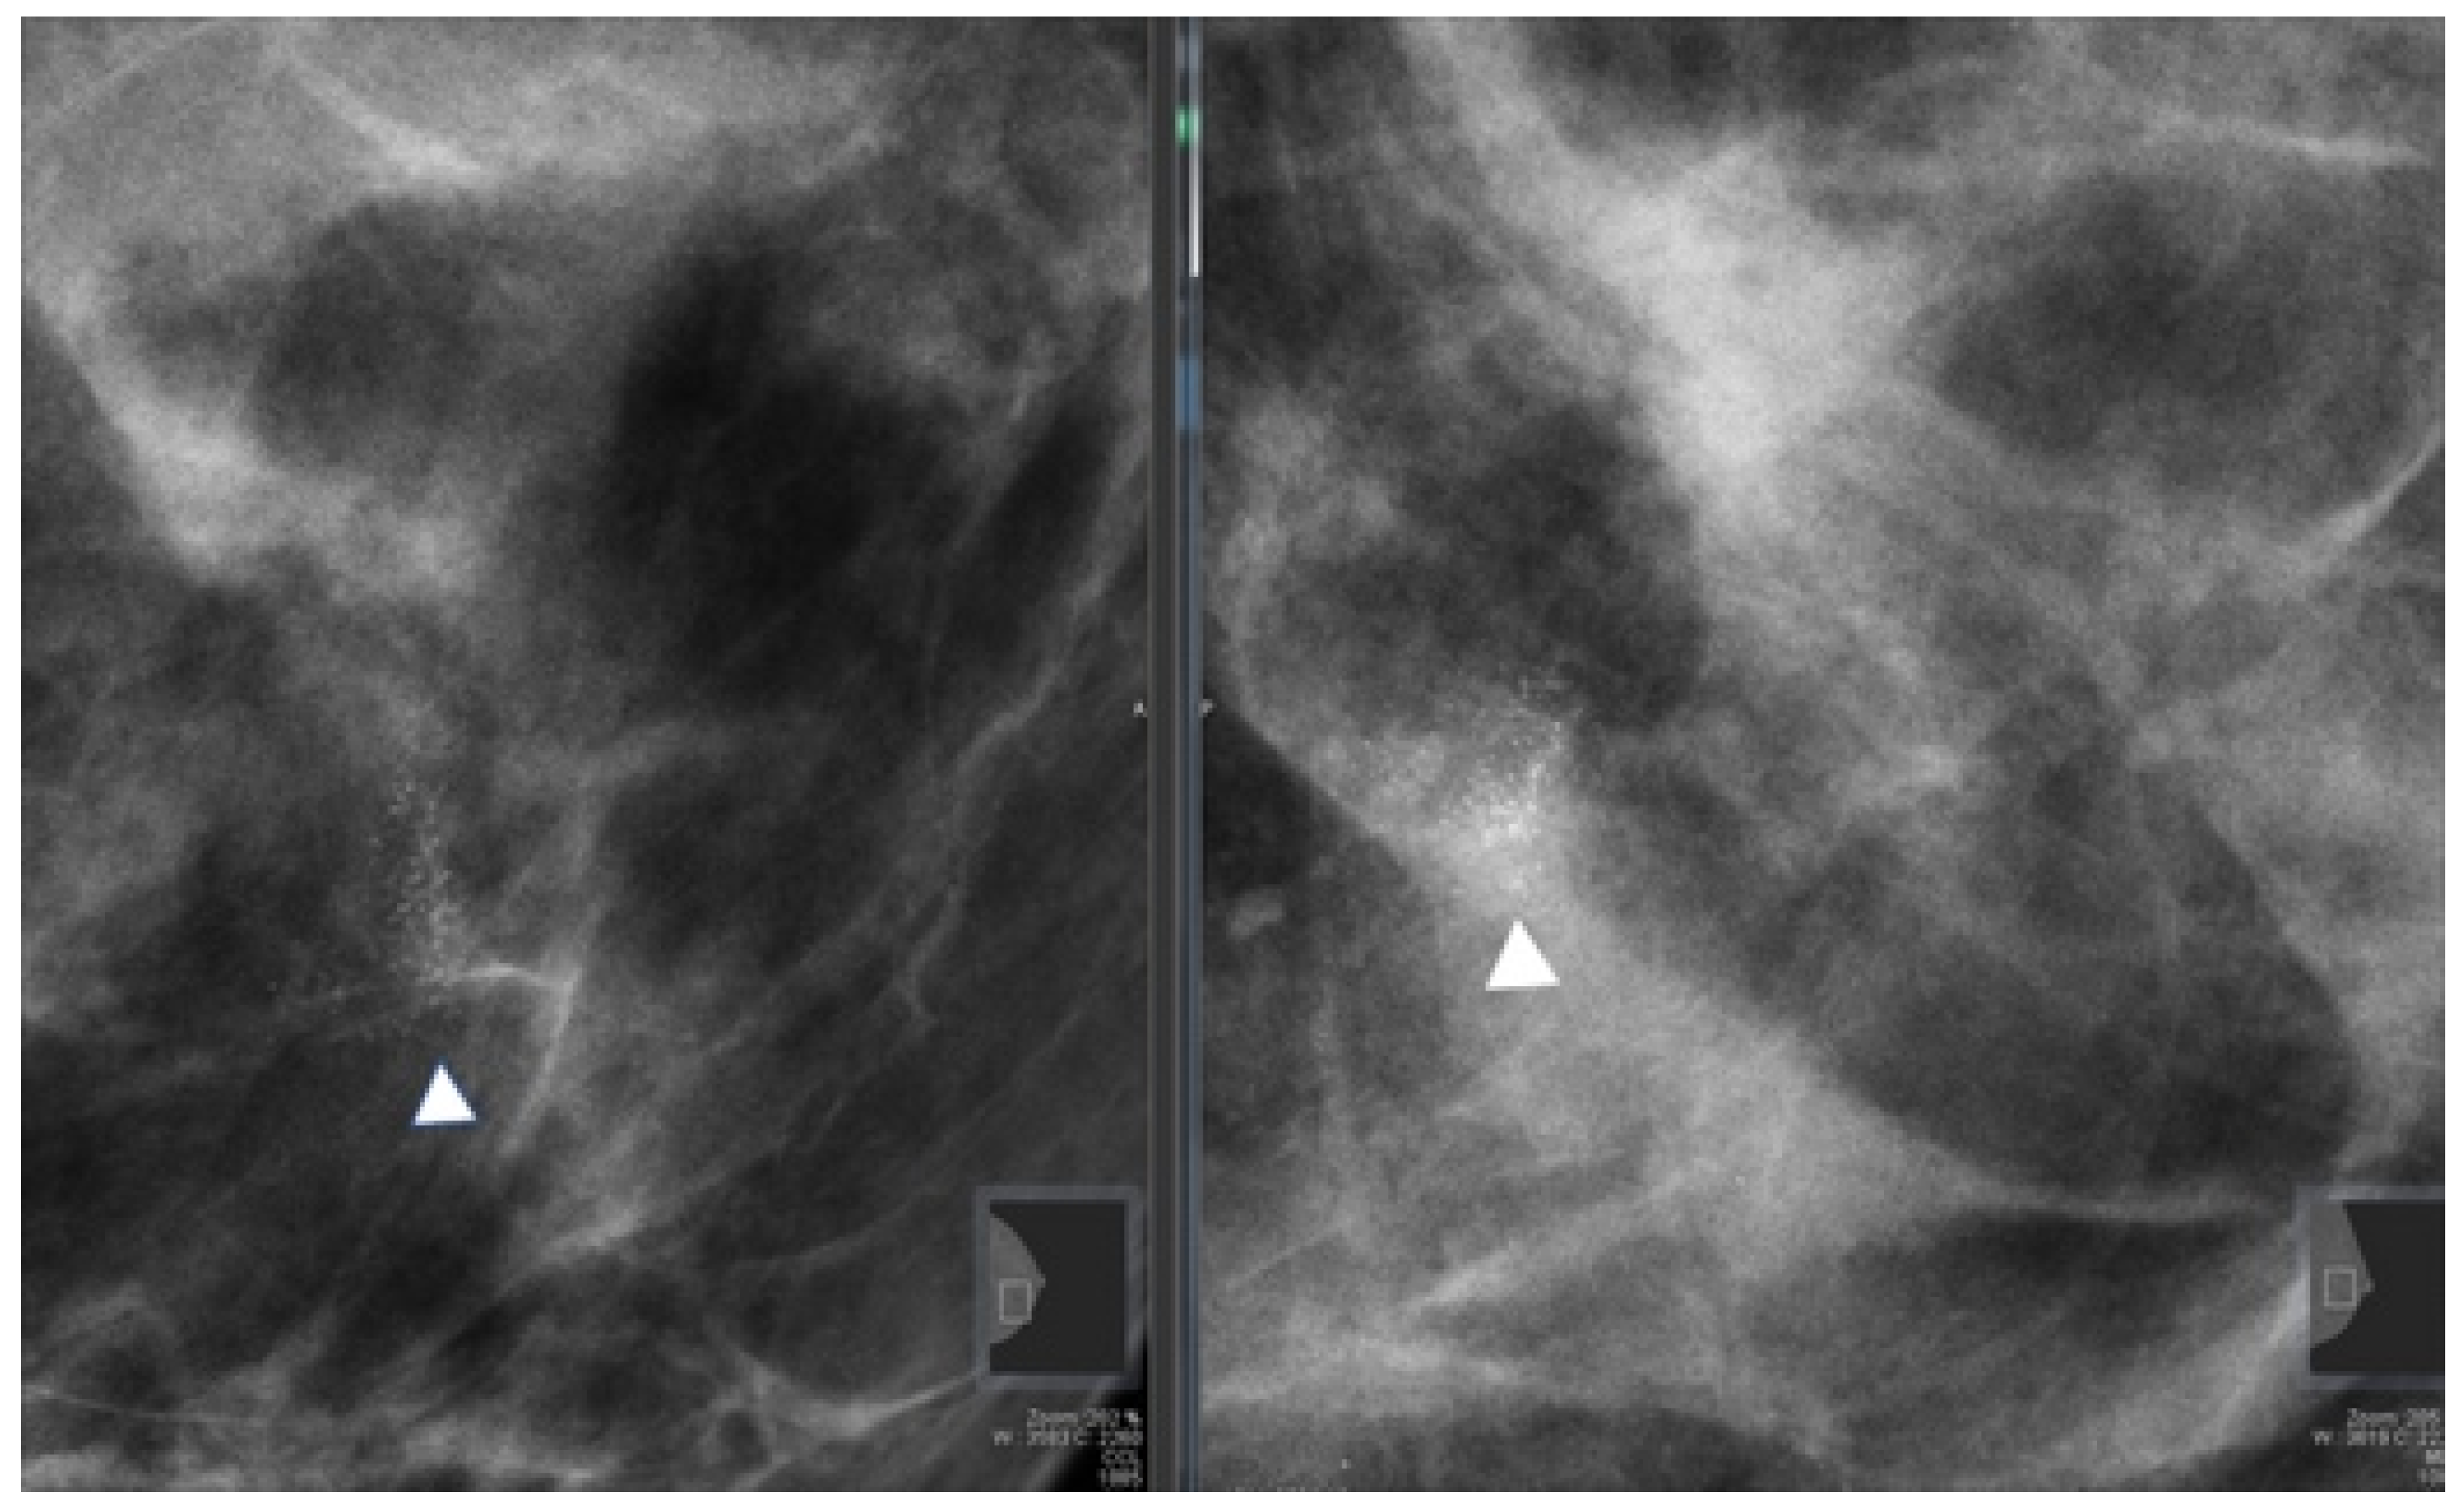

All patients who underwent stereotactic breast biopsies had two projection mammograms before the procedure (Figure 2).

Figure 2.

Full field digital mammography showing a cluster of microcalcifications (arrowhead) with a biopsy-proven histopathological result of atypical ductal hyperplasia.